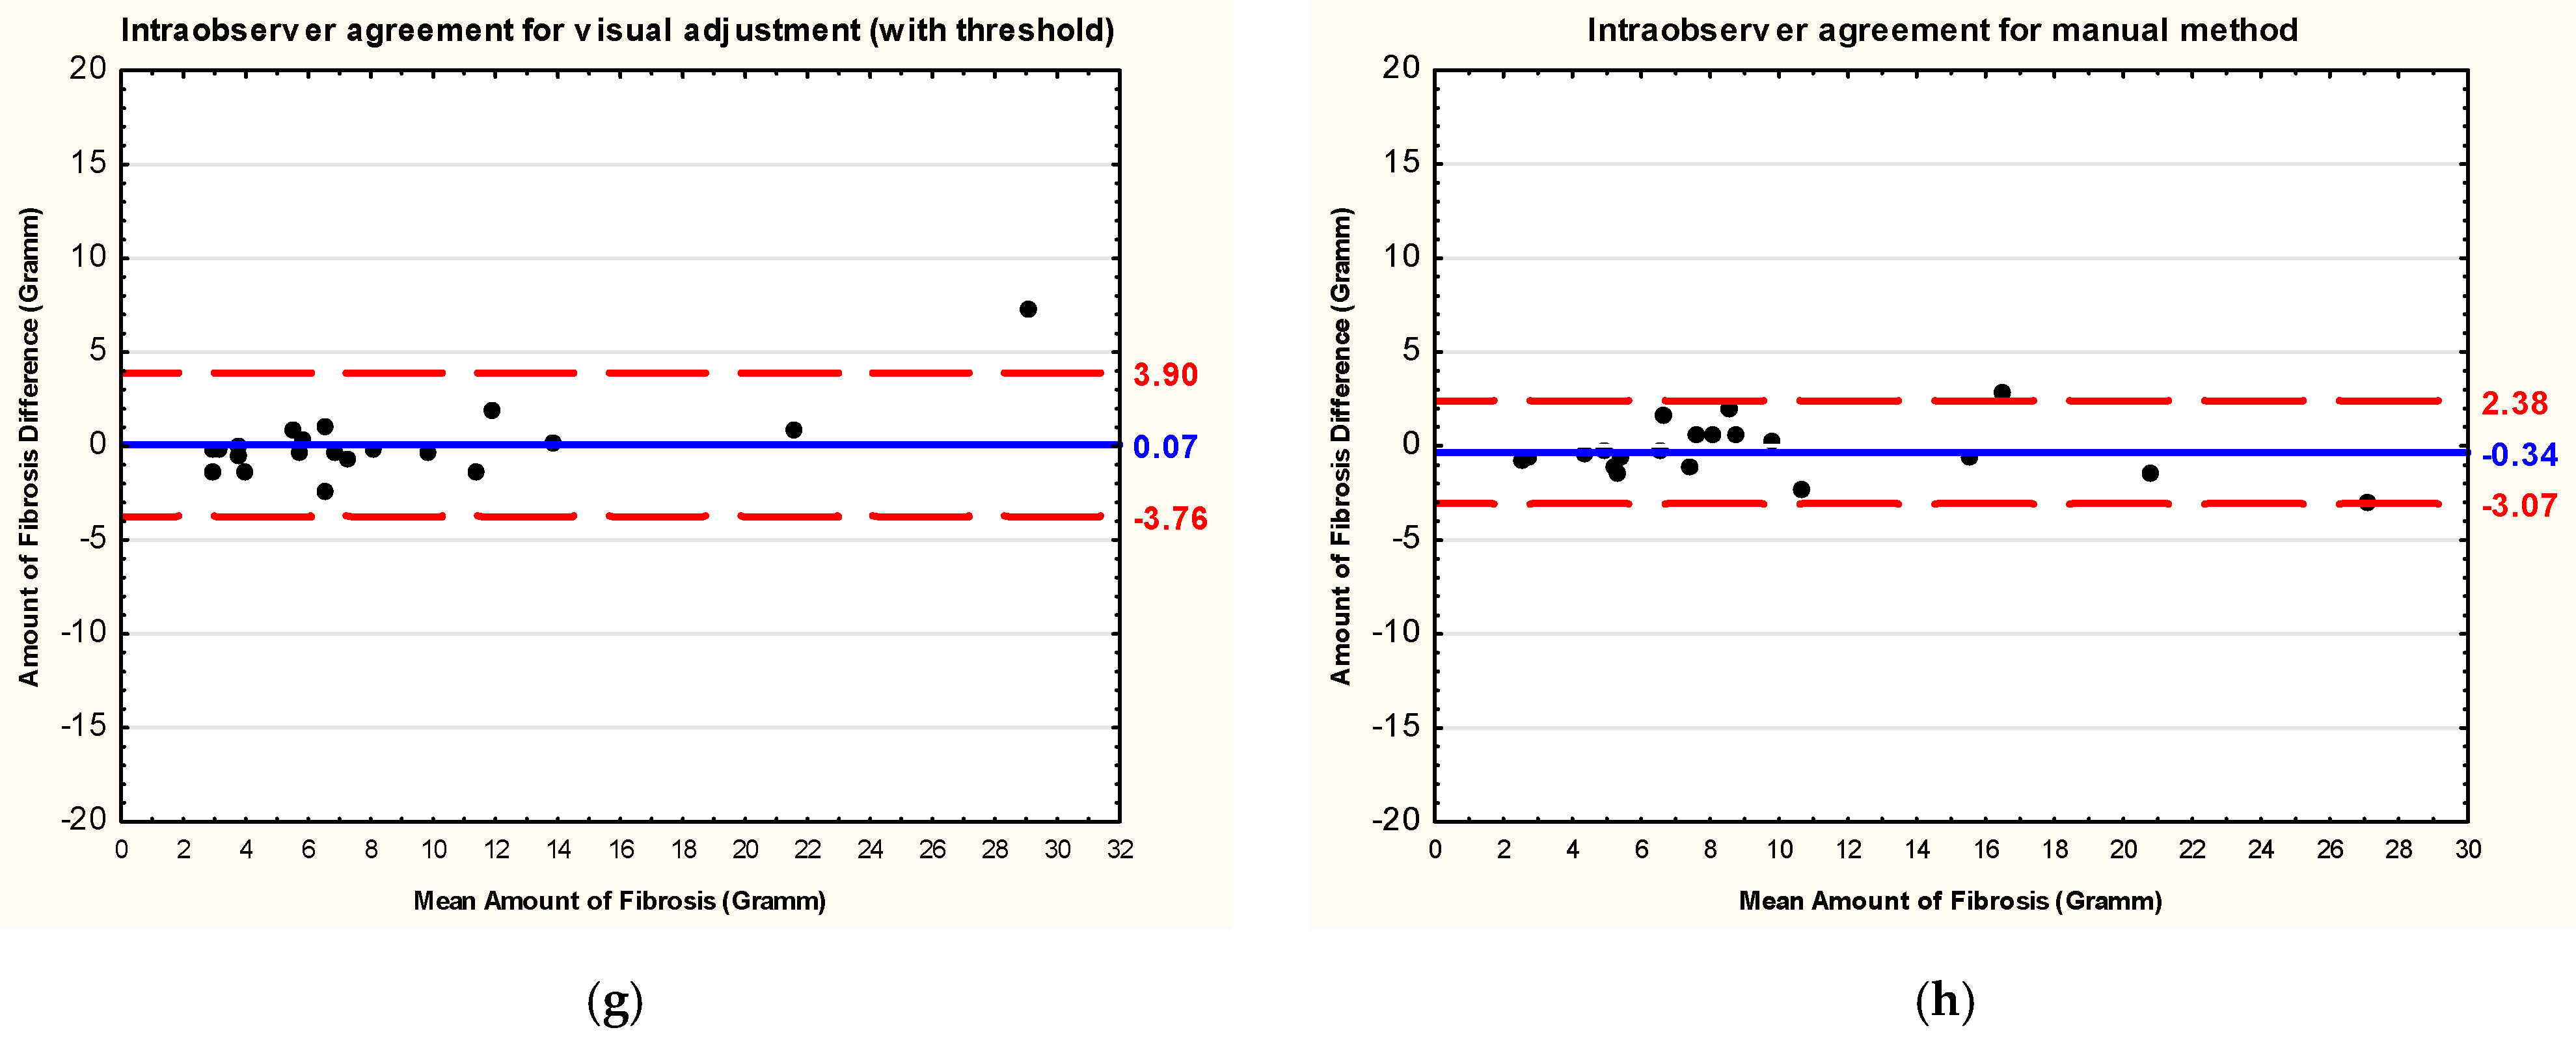

3.3. Intraobserver and Interobserver Reliability and Reproducibility